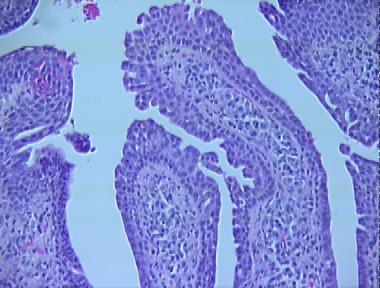

syringocystadenoma papilliferum

Histologic Features